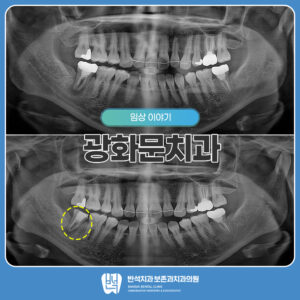

광화문치과 보철교체와 재신경치료 안녕하세요! 광화문치과의 김반석 원장입니다. 보철물은 하루에도 수천 번의 저작 압력을 견디며 뜨겁고 찬 음식, 산성 음료 등에 지속적으로 노출됩니다. 이러한 환경이 반복되면 접착력이 떨어지거나 보철물과…